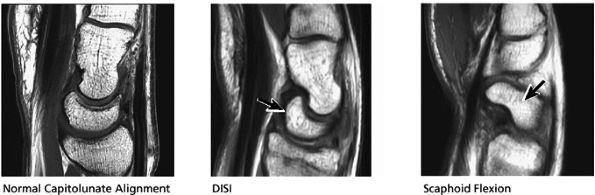

FIGURE 10.33 ● Normal sagittal anatomy. (A) The first carpometacarpal joint, visualized at the top of the field of view on sagittal images, is a common location for degenerative arthrosis. (B) Similar to the hamate, the trapezium also has a “hook,” although it is smaller and is rarely fractured. (C) An anteriorly tipped (or “flexed”) scaphoid is a sign of carpal instability, often associated with scapholunate ligament tears or scaphoid fractures. (D) DISI is suggested when the capitate lunate angle exceeds 30°. When DISI is present, the scapholunate ligament is evaluated for associated tears. (E) Sagittal images afford another opportunity to examine the hook of the hamate for fractures. (F) Triquetral fractures usually occur when the dorsal aspect of the triquetrum is avulsed by the radiotriquetral ligament. Similar to the lateral view on plain films, sagittal images demonstrate the dorsal triquetral avulsion fracture fragment. (G) Sagittal images through the abductor pollicis longus and extensor pollicis brevis tendon afford additional opportunities to identify and characterize the findings of de Quervain's stenosing tenosynovitis. (H) Occasionally, focal prominence of tortuous veins and arteries about the wrist can mimic ganglion cysts on sagittal fluid-sensitive sequences. These vessels can be distinguished from ganglions by viewing successive images and visualizing continuity of the vascular structures. (I) Tears and sprains of the dorsal and volar extrinsic capsular ligaments are optimally visualized in the sagittal plane. (J) The longitudinal extent and length of median nerve involvement in median neuritis can be measured and characterized in the sagittal plane. (K) Near its radial attachment, the triangular fibrocartilage fans out to a broad, bowtie-shaped structure, resembling the appearance of the meniscus on sagittal images of the knee. (L) Near its ulnar attachment, the triangular fibrocartilage is visualized as a short, narrow band of hypointense cartilage that represents the convergence of the dorsal and volar radial ulnar ligaments at the apex of the triangular TFC.

exceeds 30°. When DISI is present, the scapholunate ligament is evaluated for associated tears. The position of the scaphoid with respect to the rest of the carpus is also assessed. An anteriorly tipped or “flexed” scaphoid is an additional sign of DISI. When the lunate is tipped in a volar direction, with palmar translocation of the carpus, volar intercalated segmental instability (VISI) is suggested. VISI is associated with lunotriquetral ligament tears and dorsal extrinsic ligament injuries.

and tilting of the lunate or the degree of scaphoid flexion or extension. The anteroposterior location of TFC tears is determined on FS PD FSE sagittal images. Fluid in the dorsal or volar ligaments of the capsule is also shown in this plane.